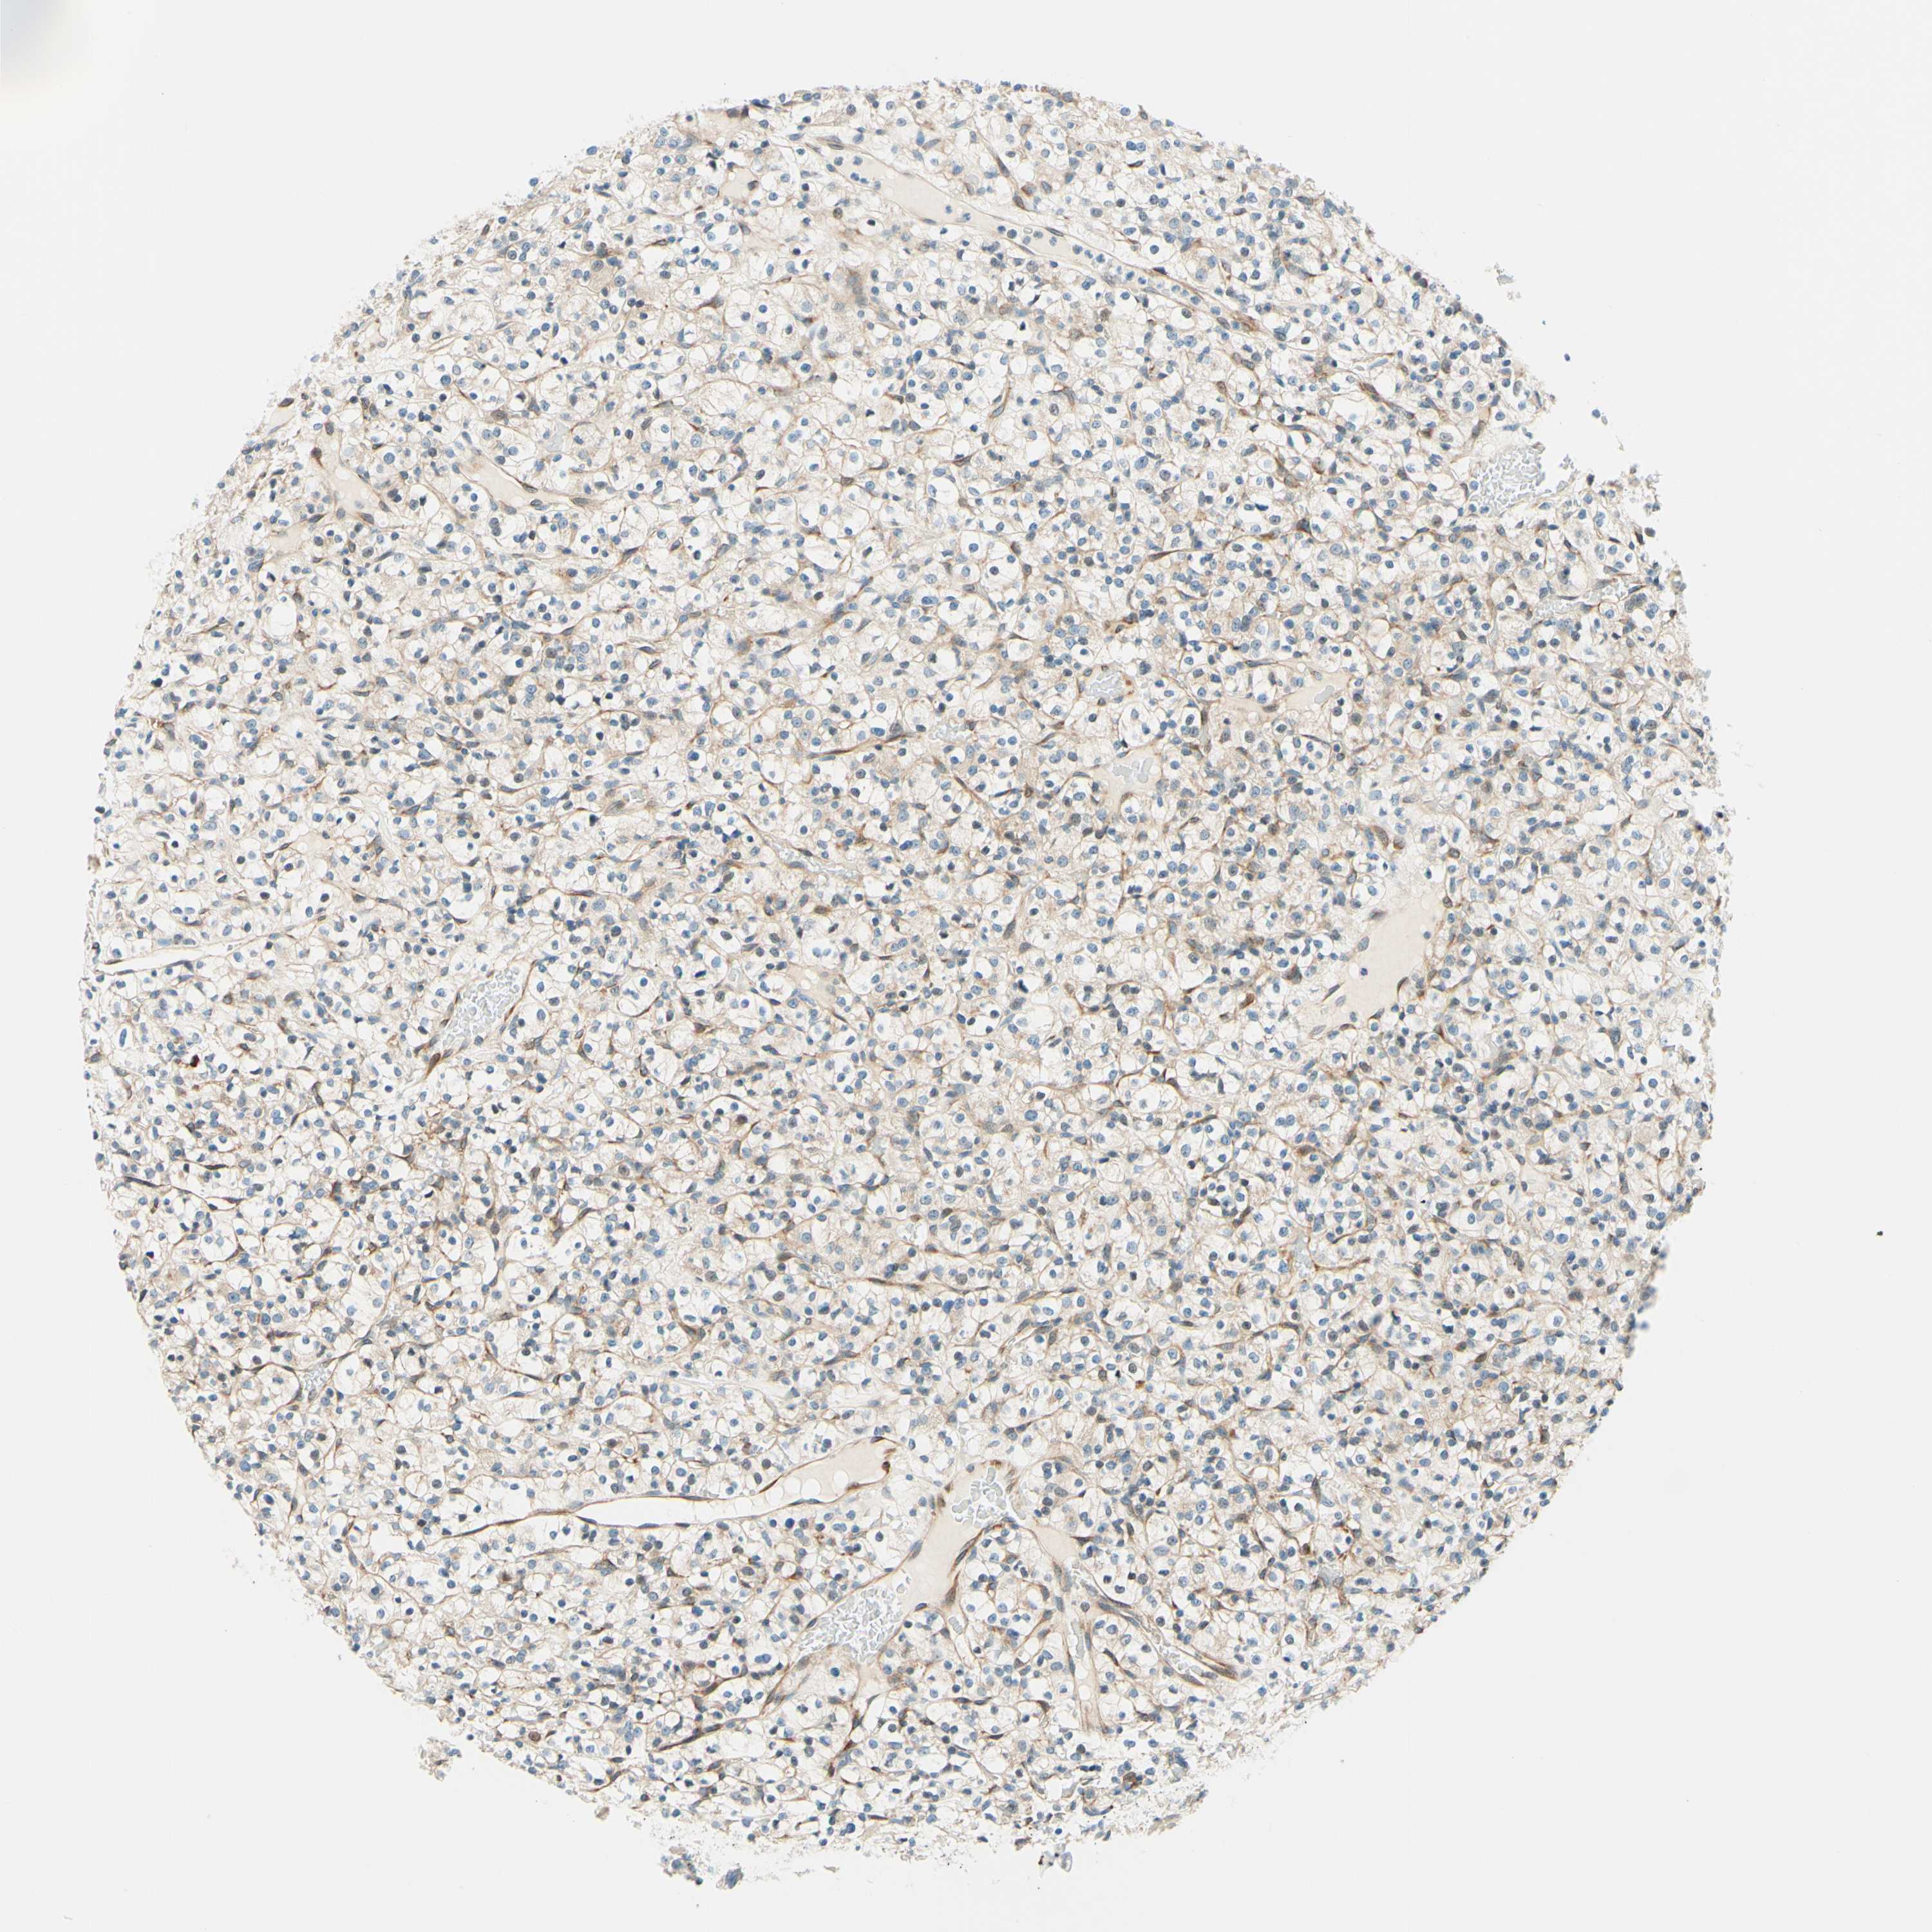

CANCER RENAL CANCER Show tissue menu

KICH TCGA KIRC TCGA KIRC VALIDATION KIRP TCGA PROTEIN RCC CPTAC PROTEIN EXPRESSION

KIDNEY CHROMOPHOBE (TCGA) - Interactive survival scatter ploti

The Survival Scatter plot shows the clinical status (i.e. dead or alive) for all individuals in the patient cohort, based on the same data that underlies the corresponding Kaplan-Meier plots. Patients that are alive at last time for follow-up are shown in blue and patients who have died during the study are shown in red.

The x-axis shows the expression levels (FPKM) of the investigated gene in the tumor tissue at the time of diagnosis. The y-axis shows the follow-up time after diagnosis (years). Both axes are complimented with kernel density curves demonstrating the data density over the axes. The top density plot shows the expression levels (FPKM) distribution among dead (red) and alive patients (blue). The right density plot shows the data density of the survived years of dead patients with high and low expression levels respectively, stratified using the cutoff indicated by the vertical dashed line through the Survival Scatter plot. This cutoff is automatically defined based on the FPKM cutoff that minimizes the p-score. The cutoff can be changed by dragging the vertical line or by entering a cutoff value in the square labeled "Current cut-off".

Under the Survival Scatter plot the p-score landscape (black curve; left axis) is shown together with dead median separation (red curve; right axis). Dead median separation is the difference in median mRNA expression between patients who have died with high and low expression, respectively. It is calculated as follows: median FPKM expression of dead patients with high expression - median FPKM expression of dead patients with low expression. This is intended to aid the user in visually exploring custom cutoffs and the associated p-scores and dead median separation.

Individual patient data is displayed and can be filtered by clicking on one or more of the category buttons on the top of the page. Categories describing expression level and patient information include: high, low, alive, dead, female, male and tumor stages. The scale of the x-axis can be toggled between linear and log-scale by clicking on the "x log" button. Mouse-over function shows TCGA ID, patient information and mRNA expression (FPKM) for each patient.

& Survival analysisi

Kaplan-Meier plots summarize results from analysis of correlation between mRNA expression level and patient survival. Patients were divided based on level of expression into one of the two groups "low" (under cut off) or "high" (over cut off). X-axis shows time for survival (years) and y-axis shows the probability of survival, where 1.0 corresponds to 100 percent.

TAOK2 is not prognostic in Kidney Chromophobe (TCGA)

Average pTPM 30.8

Number of samples 64